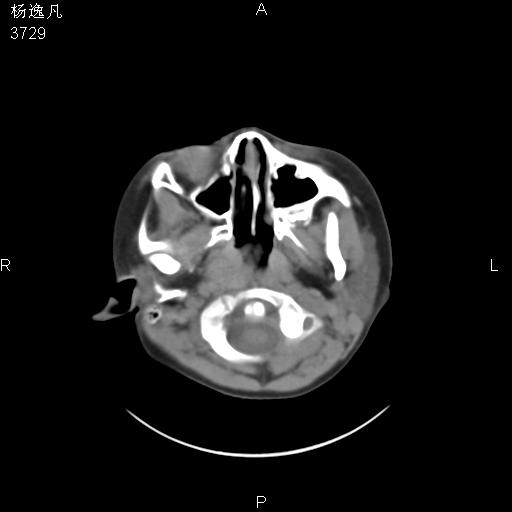

男性,5岁,面部受外伤,余无特殊

骨窗

1、右面部及颞部软组织肿胀。

2、腺样体肥大。

头颅ct平扫未见明确外伤性征象,右侧面部及颞部软组织肿胀,后鼻腔软组织影增大,增厚,鼻咽顶部变窄,考虑鼻咽腺样体增值肥厚。

双侧位置太不对称,未见明显骨折征象。